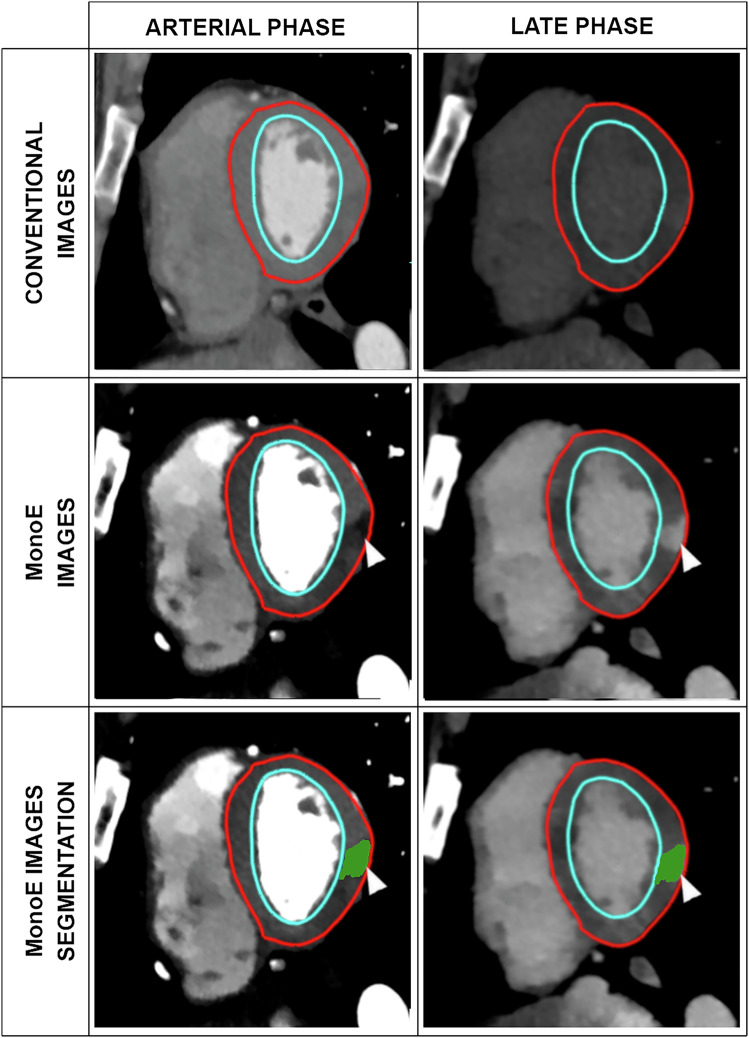

Materials and methods: Forty-seven cardiac spectral CTs performed in patients with magnetic resonance imaging (MRI)-confirmed myocarditis were retrospectively assessed. Three myocardial attenuation/enhancement patterns were visually identified and segmented on both arterial and LE acquisitions: hypodense-arterial + normal-LE (HypoArt-NorLE); normal-arterial + hyperdense-LE (NorArt-HyperLE); and hypodense-arterial + hyperdense-late (HypoArt-HyperLE). Characteristics of conventional and spectral images were calculated for all patterns and for remote myocardium. Values of HypoArt-HyperLE lesions were compared in the groups with and without edema on MRI, as assessed with T2 mapping (available for 25 patients).

Results: We found 173 lesions, 46 (26%) HypoArt-NorLE, 54 (31%) NorArt-HyperLE, and 73 (42%) HypoArt-HyperLE. On the arterial phase, HypoArt-HyperLE were more hypodense (p < 0.001) and had less iodine (0.23 mg/mL less; p < 0.001) than RM. On LE, both HypoArt-HyperLE and NorArt-HyperLE were more hyperdense and contained more iodine than the remote myocardium (all p < 0.001). HypoArt-HyperLE lesions were more hypodense and contained less iodine on the arterial phase in patients with edema on MRI as compared to those without (all p < 0.001).

Conclusion: Most myocarditis lesions detectable with spectral CT are visible on both arterial and LE acquisitions. These lesions appeared to be more pronounced on the arterial phase in patients with edema on MRI.

Relevance statement: Spectral CT arterial acquisition performed for the differential diagnosis of acute myocardial pathologies in many cases can depict myocarditis lesions as epicardial hypodense areas, most likely related to the presence of edema.

Key points: Data from spectral CT shows that most myocarditis lesions appear as hypodense on the arterial phase, matching the epicardial LE zones. A minority of myocarditis lesions appear as epicardial LE areas without anomalies of attenuation on the arterial phase. Hypodense myocardial areas are correlated to the presence of edema on MRI, suggesting they are due to the same phenomenon.